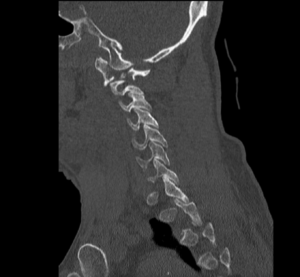

CSpine Fracture CT Sagital Unannotated. JETem 2025